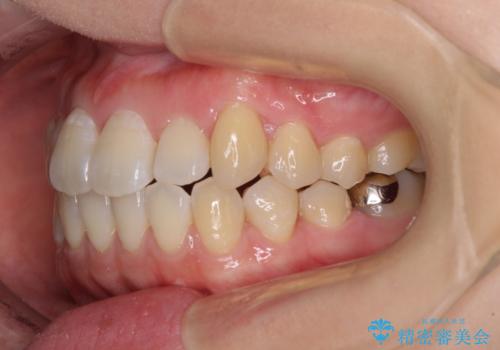

インビザラインでの歯列全体の後方移動は時間がかかりますが、しっかりと装着時間を守っていただいたので、スッキリとした口元に仕上げることができました。